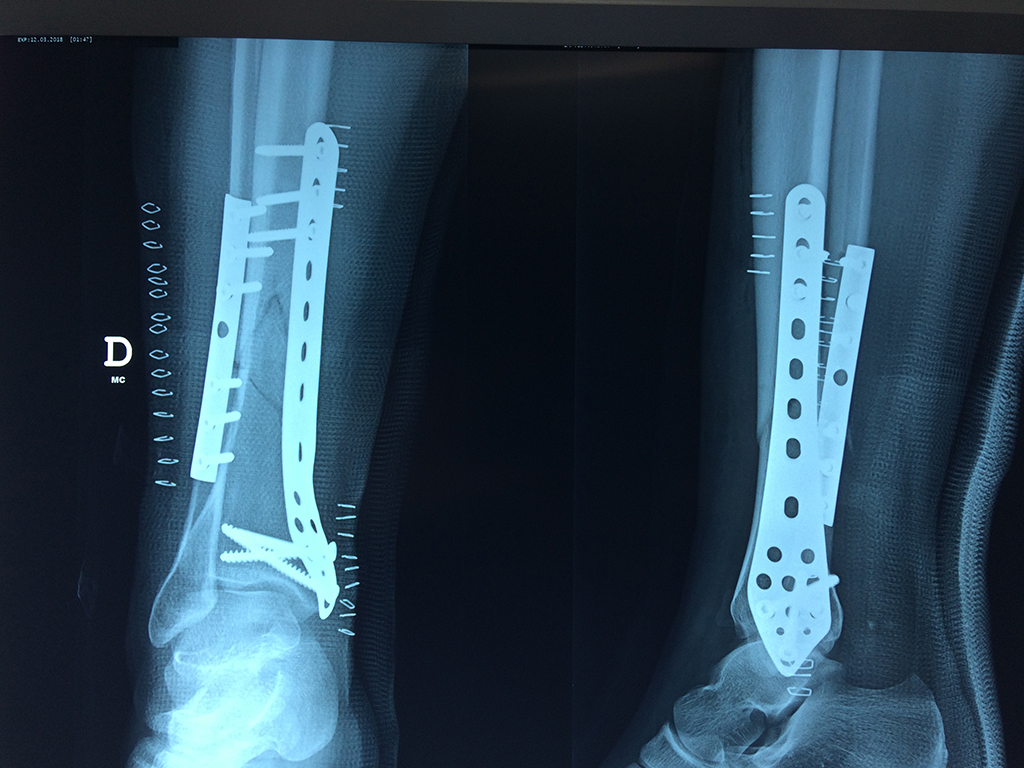

Cirugías de Calcaneo - Perone y Tibia

Aunque cada uno de estos huesos puede fracturarse por separado, normalmente la rotura es una lesión que se produce de forma conjunta

La mayor parte de las roturas implican a la parte proximal del hueso (parte del hueso próximo a la rodilla) o a la parte distal (parte del hueso cerca del tobillo).

Debido a la fina cobertura de piel que recubre la tibia y el peroné, las fracturas generalmente son abiertas, es decir, el hueso roto rasga la piel, atravesándola. Las fracturas de tibia y peroné generalmente se producen por un fuerte impacto o torsión.